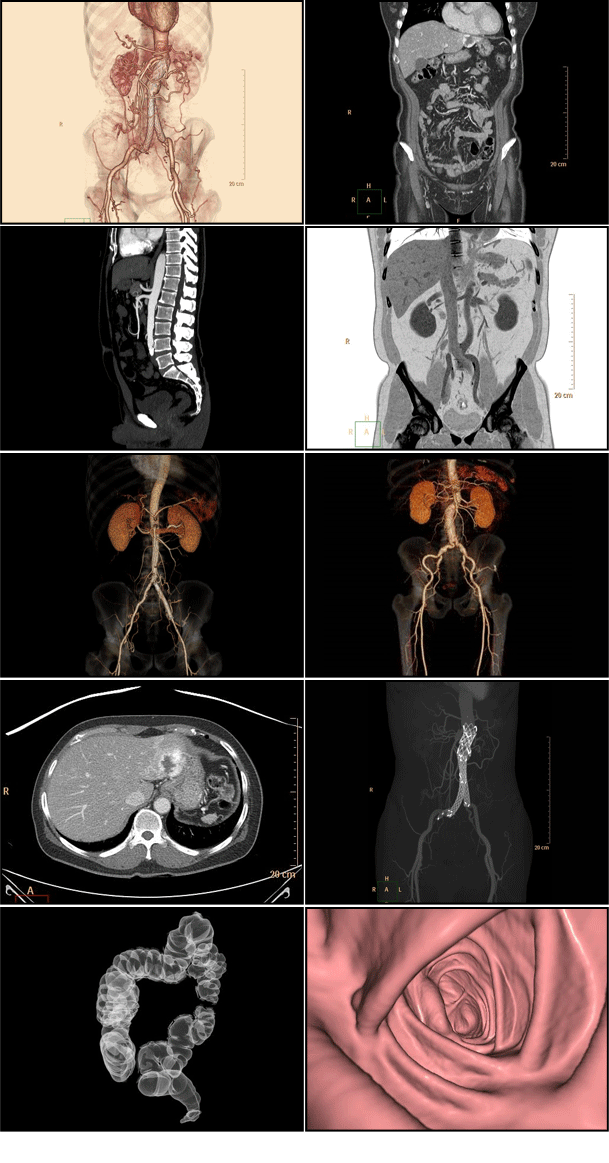

• 3차원복부CT

3차원복부CT